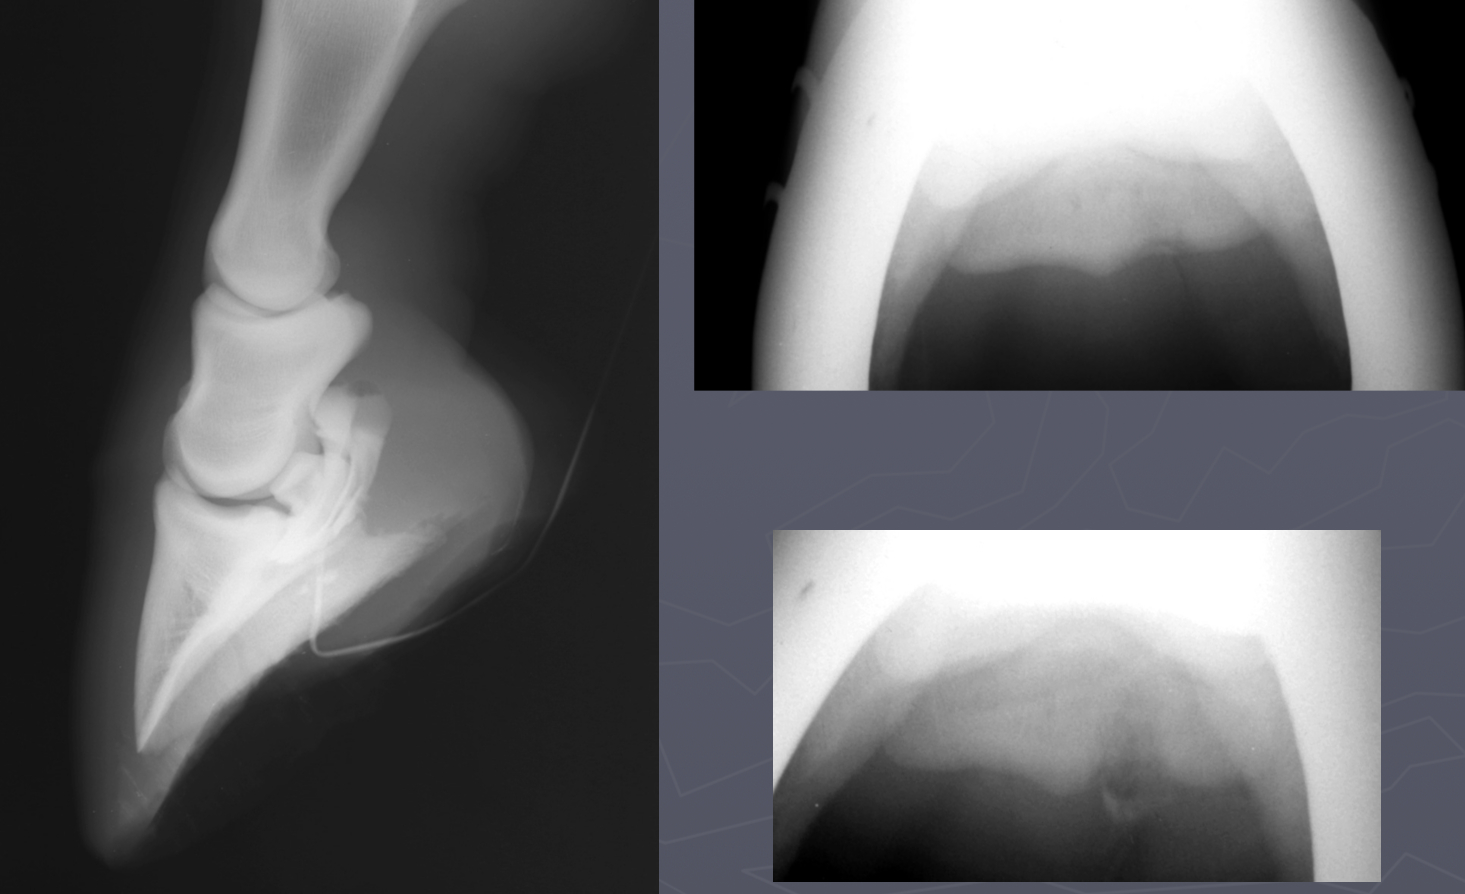

Hypertrophic Osteopathy